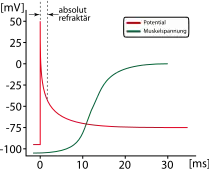

| Response to stimulus |  |

|

|